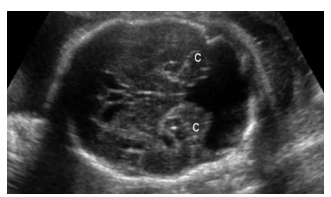

Ao realizar o exame ecográfico obstétrico de uma gestante 37 semanas, você se depara com a seguinte imagem. Assinale a alternativa correta.

Enunciado 4614329-1